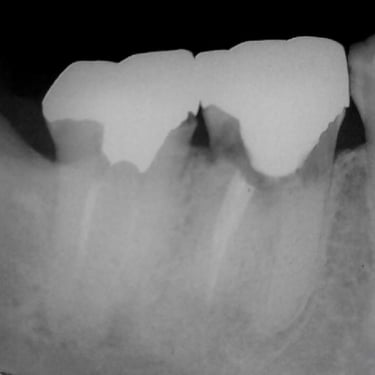

Lesión Endo-Perio Combinada

Una lesión endo-perio combinada es una condición en la que hay tanto una infección de la pulpa como una enfermedad periodontal.

Los pacientes pueden experimentar dolor, hinchazón y movilidad dental.

El tratamiento incluye tanto el tratamiento de conducto como el tratamiento periodontal para abordar ambas infecciones. La coordinación entre el endodoncista y el periodoncista es esencial.